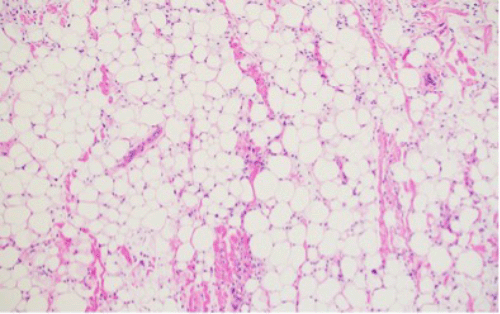

Figure 2. Immunohistochemical Stains of Soft Tissue Mass Biopsy. Published with Permission

A higher-power view (100x magnification) further details the adipocytic tissue, lipoblasts, and primitive ovoid stromal cells within the myxoid stroma

mmunohistochemical stain for CD34 (100x magnification) demonstrating diffuse positive staining within the spindled stromal cell component and capillary endothelium